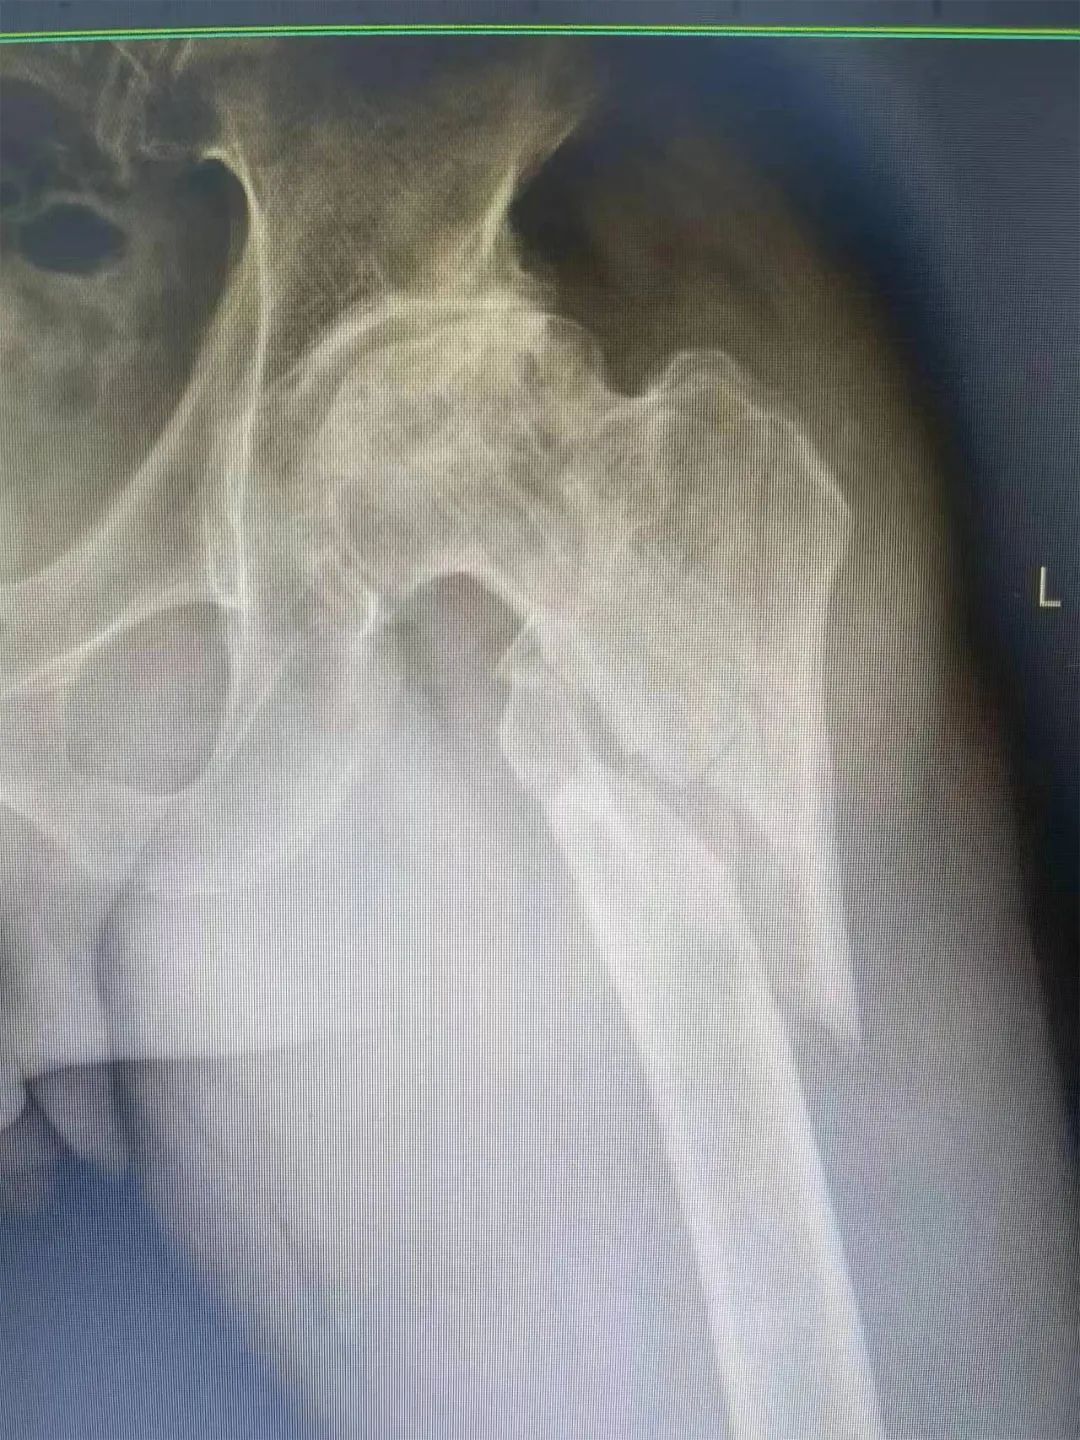

入院后,骨科张云奇主任带领主治医师刘贾昆、主治医师刘志鹏立刻对患者进行详细查体,患者目前处于生命体征平稳,睡眠一般,左髋部外旋畸形、肿胀,主动活动障碍状态。随后,张云奇主任详细询问患者病史及受伤过程,诊断该患者为左侧股骨转子间转子下骨折。结合患者的临床表现情况,目前首选的治疗方案为仿生双动全髋关节置换手术。 ▲患者术前影像 三亚哈医大樱花动漫

骨科团队在高龄合并多种疾病骨折手术领域拥有丰富的手术经验与临床经验,已为数百位高龄患者成功实施手术。三亚哈医大樱花动漫